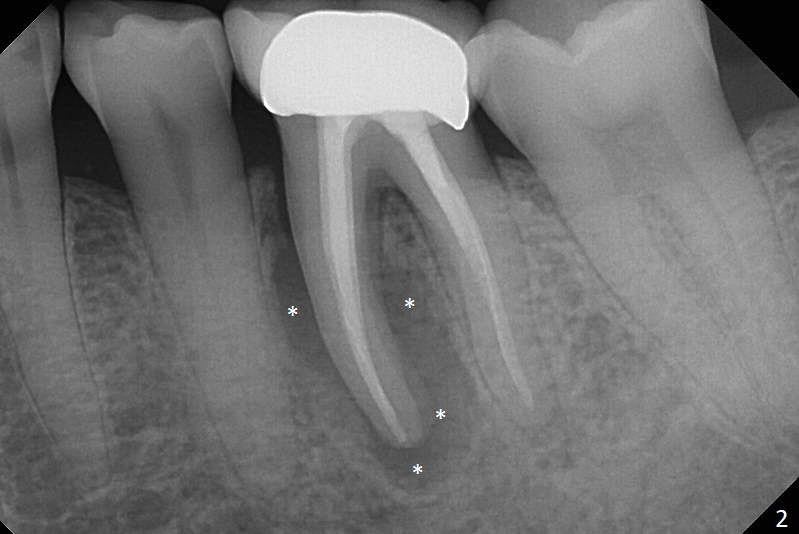

When the patient returns 9 months later, there is severe buccal gingival recession and abscess at #19 (Fig.1 *) with large mesial periradicular radiolucency (Fig.2 *).  The septum is thin and the buccal crest is low after extraction (Fig.3 * (mesial root vertical fracture)).  Osteotomy is initiated in the mesial socket immediately against the septum (Fig.4.5) with ~ 5 mm in the native bone.  Due to severe buccal plate resorption, a shorter implant is placed (Fig.6; 5x15 mm in stead of 18 mm).  There is at least 2 mm gap buccally for Vanilla Graft, which is also placed next to the implant and the neighboring root (Fig.7 *).  There is clearance from the Inferior Alveolar Canal (Fig.8 red dashed line).  Both the mesial and distal sockets heal 5.5 months postop (Fig.9), although the apical portion of the distal socket was not filled with allograft (Fig.7).  The implant was placed mesial.  The straight abutment (6.5x4(4) mm) (Fig.10) is changed to an angled one (5.5 x15 degrees 3 mm cuff (Fig.11)) before impression.  The implant is also placed buccally.  Therefore the implant position is far more important than its length.  The abutment is retightened 2.5 months post cementation, which is related to mesiobuccal placement of the implant (Fig.12).  An ideal trajectory is determined by drawing 2 horizontal lines (at crestal and apical levels: red lines in Fig.13), finding a central point of each line (vertical short line) and joining these 2 central points (Fig.14 pink line).  In fact the ideal osteotomy should have been established distal to the septum in this case.  Guided surgery may alleviate the issue.  The crown is not loose, but the patient feels that the implant tooth cannot sustain mastication.  In fact the screw is removed with hand driver (not wrench).  The abutment hex is rounded and worn.  A new 5.5x4(4) mm abutment is placed (without knowledge of previous use of an angled abutment) with mesial reduction to reduce undercut and buccodistal margin lowered to reduce gingival embrasure. It is that the straight abutment could decrease the chance of screw loosening.  Otherwise the implant has to be removed for better trajectory.